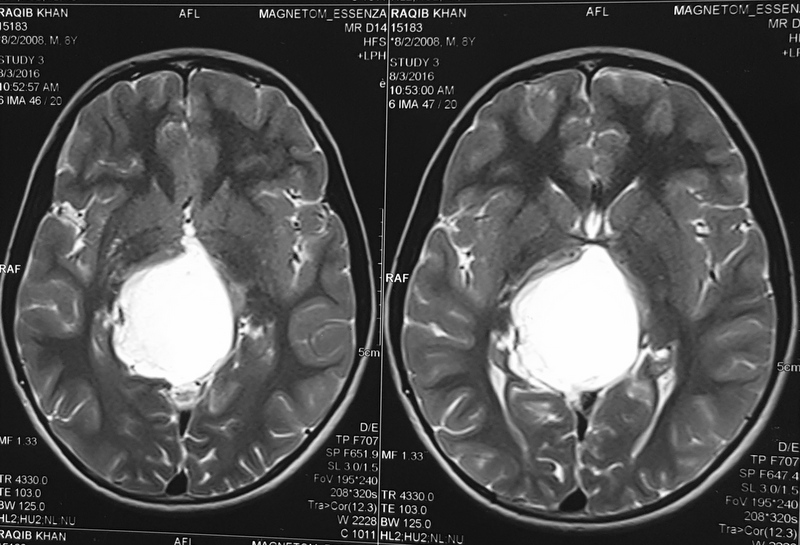

Pilocytic astrocytoma of Posterior Third Ventricle

A 9-year-old male child was evaluated for recurring headaches. Clinically, he had papilloedema. Imaging studies (Figs 1 to 3a & b) showed large posterior third ventricular tumor exhibiting peripheral rim contrast enhancement. The tumour was excised under general anaesthesia, in sitting position, by Supracerebellar Infratentorial approach. The tumour could be excised completely. He has been followed up, and MRI after three years showed only postoperative changes and no tumour residue (Figs 4a & b).

Fig 1

(Fig 1)